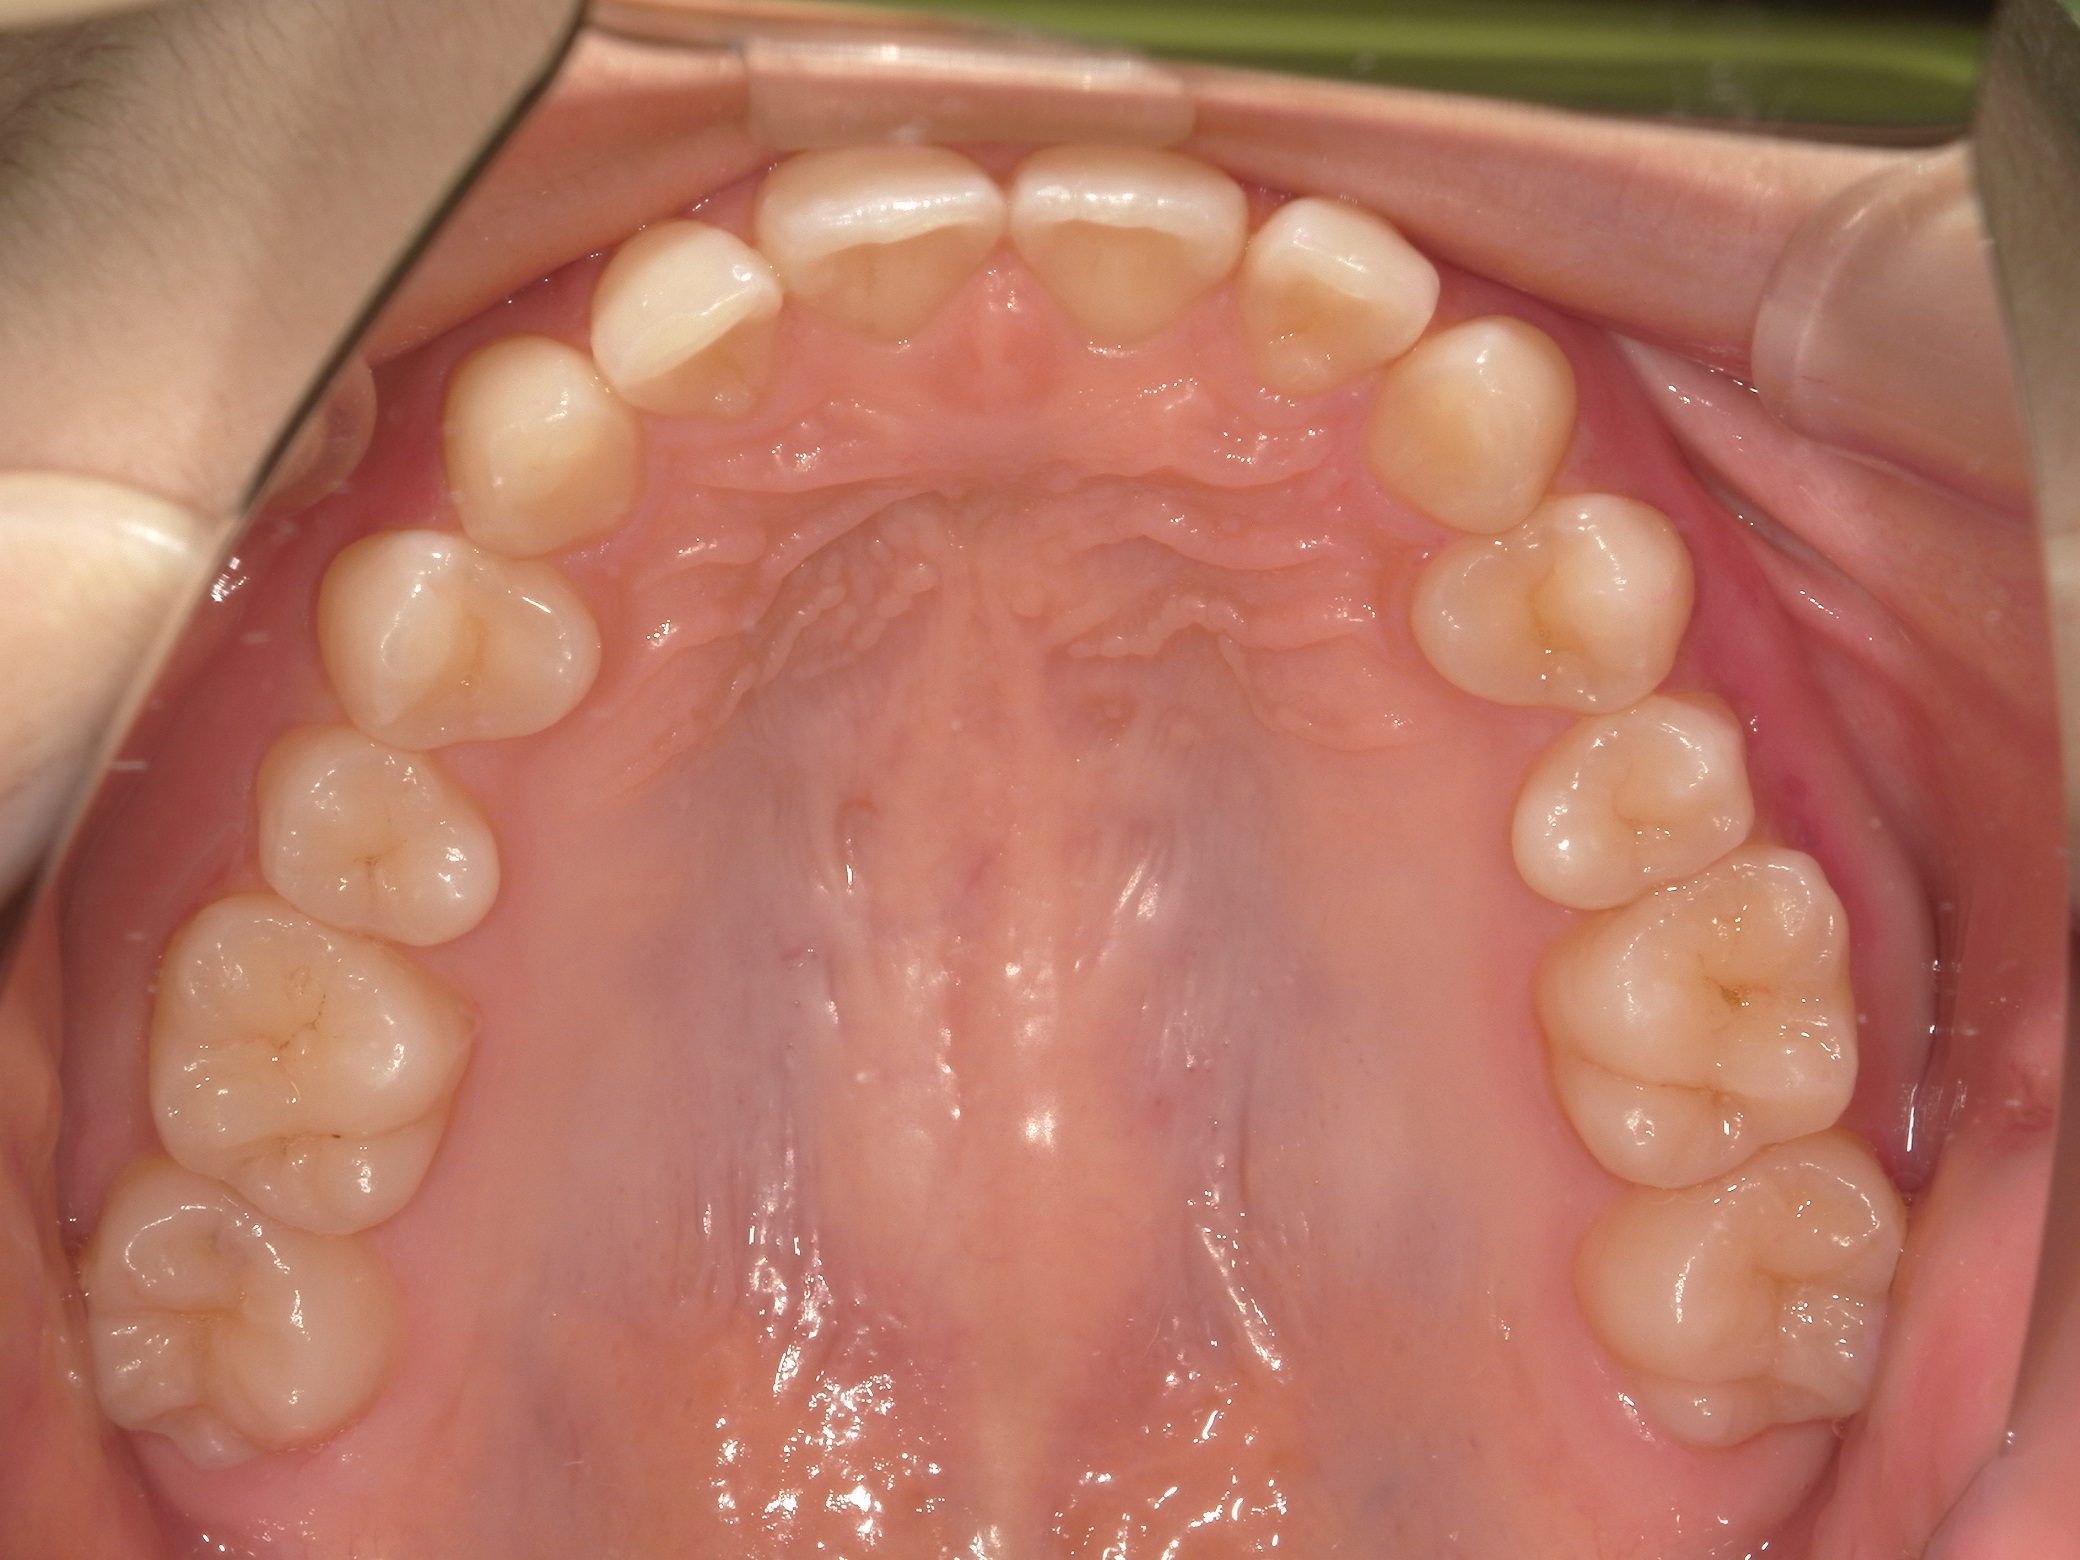

【小学生】マイオブレース矯正 上顎前突(出っ歯)と叢生(でこぼこ)を改善

小学生で開始

マイオブレース

でこぼこ

出っ歯

過蓋咬合

非抜歯

1期治療のみで改善

Before

After

治療期間

2.1年

治療開始

8歳

種類

マイオブレース矯正

使用装置

機能矯正装置

コメント

咬み合わせのズレを改善するために 矯正をされました

しっかり取り組んでくれてスムーズに終了しました